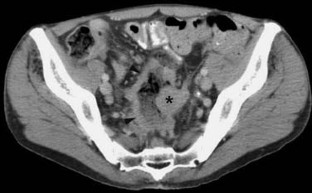

Fig. 1